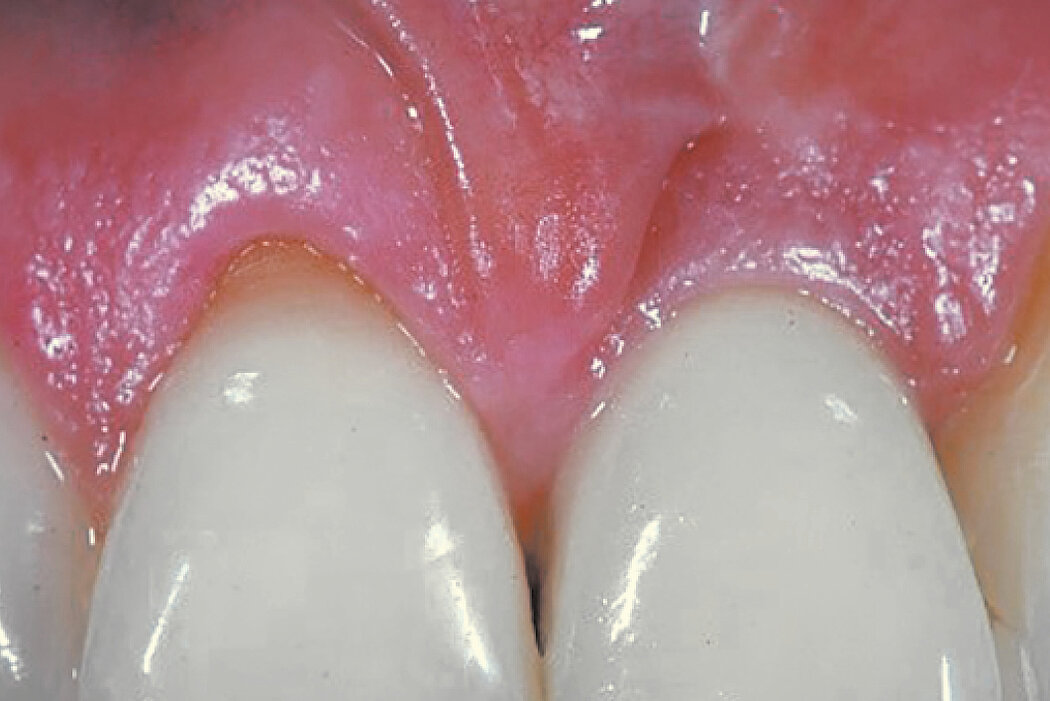

颊侧骨壁完整时的牙槽窝内牙槽嵴保存

病例来自 Dr. Hadi Antoun & Dr. Bouchra Sojod

法国,巴黎

临床挑战

使用选定的生物材料,保存前牙区的硬组织和软组织,以便进行延迟种植。

目的/方法

拔牙后的硬组织和软组织保存。延迟种植是一种非常可靠的手术,国际文献中已反复证实了这一点。

结论

Geistlich Bio-Oss® Collagen 和 Geistlich Mucograft® Seal 在术后5个月可实现牙槽嵴保存,为种植体固定提供最佳条件。在中切牙处,使用结缔组织移植物优化颊侧软组织厚度。

拔牙前与拔牙后2年的比较